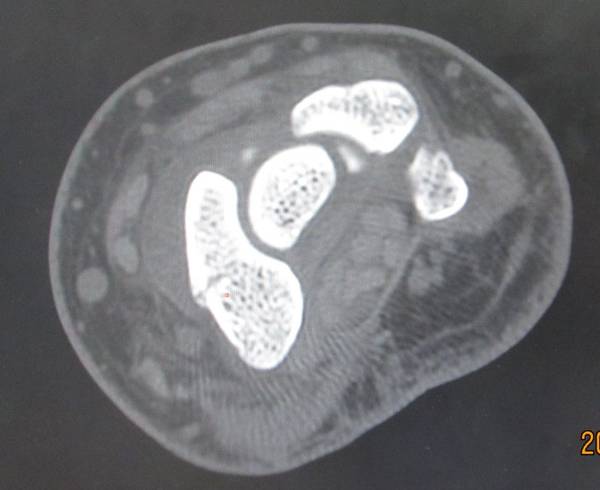

今天去ct室拍了一组舟骨骨图片

在机房看的动态的图像,想怎么看就怎么看

随便转

对骨质结构情况一目了然

太清楚了

4.png

2.png

1.png

3.png

zhangwenlong 发表于 2012-7-8 00:53

可以做个人的手,把手部的所有血管啊骨的重建起来,考个光盘回家,想怎么看都可以!